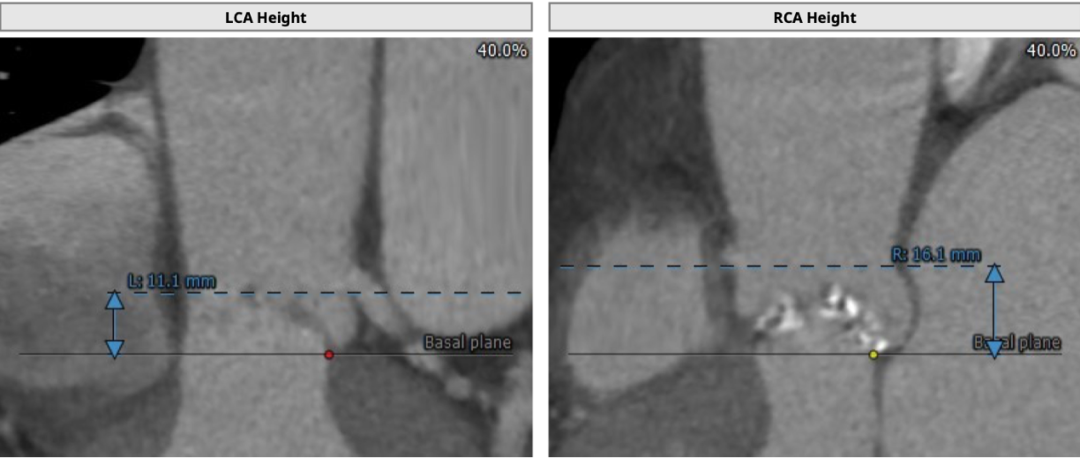

为TYPE1型二叶式主动脉瓣,左右融合钙化嵴,钙化较重,瓣环周长获得平均直径25.1mm,左右冠脉开口高度分别为11.1和16.1mm。左冠开口水平可见瓣叶,有堵塞风险。双侧股动脉无明显钙化迂曲,左右最细处分别为5.7和5.8mm。